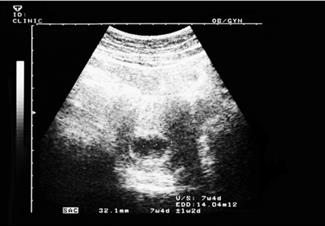

מאת: מערכת אינפומד 19/02/2019אם עדיין לא עשית אולטרסאונד, השבוע תפגשי לראשונה את העובר שלך. מה תוכלי לראות באולטרסאונד ומה את צפויה להרגיש בשבוע... לכתבה המלאה